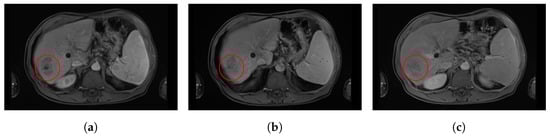

Blood flow in HCC typically passes through the lesion and into the venous outflow faster than in a healthy liver, leading to a peak in tumour enhancement in the late arterial phase followed by a characteristic “washout” that allows us to observe a tumour hyposignal relative to the liver at the portal venous and delayed phases (Figure 1).

Figure 1.

Evolution of tumour enhancement post-contrast agent injection in an axial slice of a contrast-enhanced magnetic resonance imaging (CE-MRI) from the same patient. This figure shows the evolution over time of the tumour enhancement in the red circle. (a) Axial CE-MRI slice at arterial time. (b) Axial CE-MRI slice at portal time. (c) Axial CE-MRI slice at delayed time (c). One may notice the enhancement in the tumour in arterial time acquisition, slowly vanishing in portal time and delayed acquisitions.